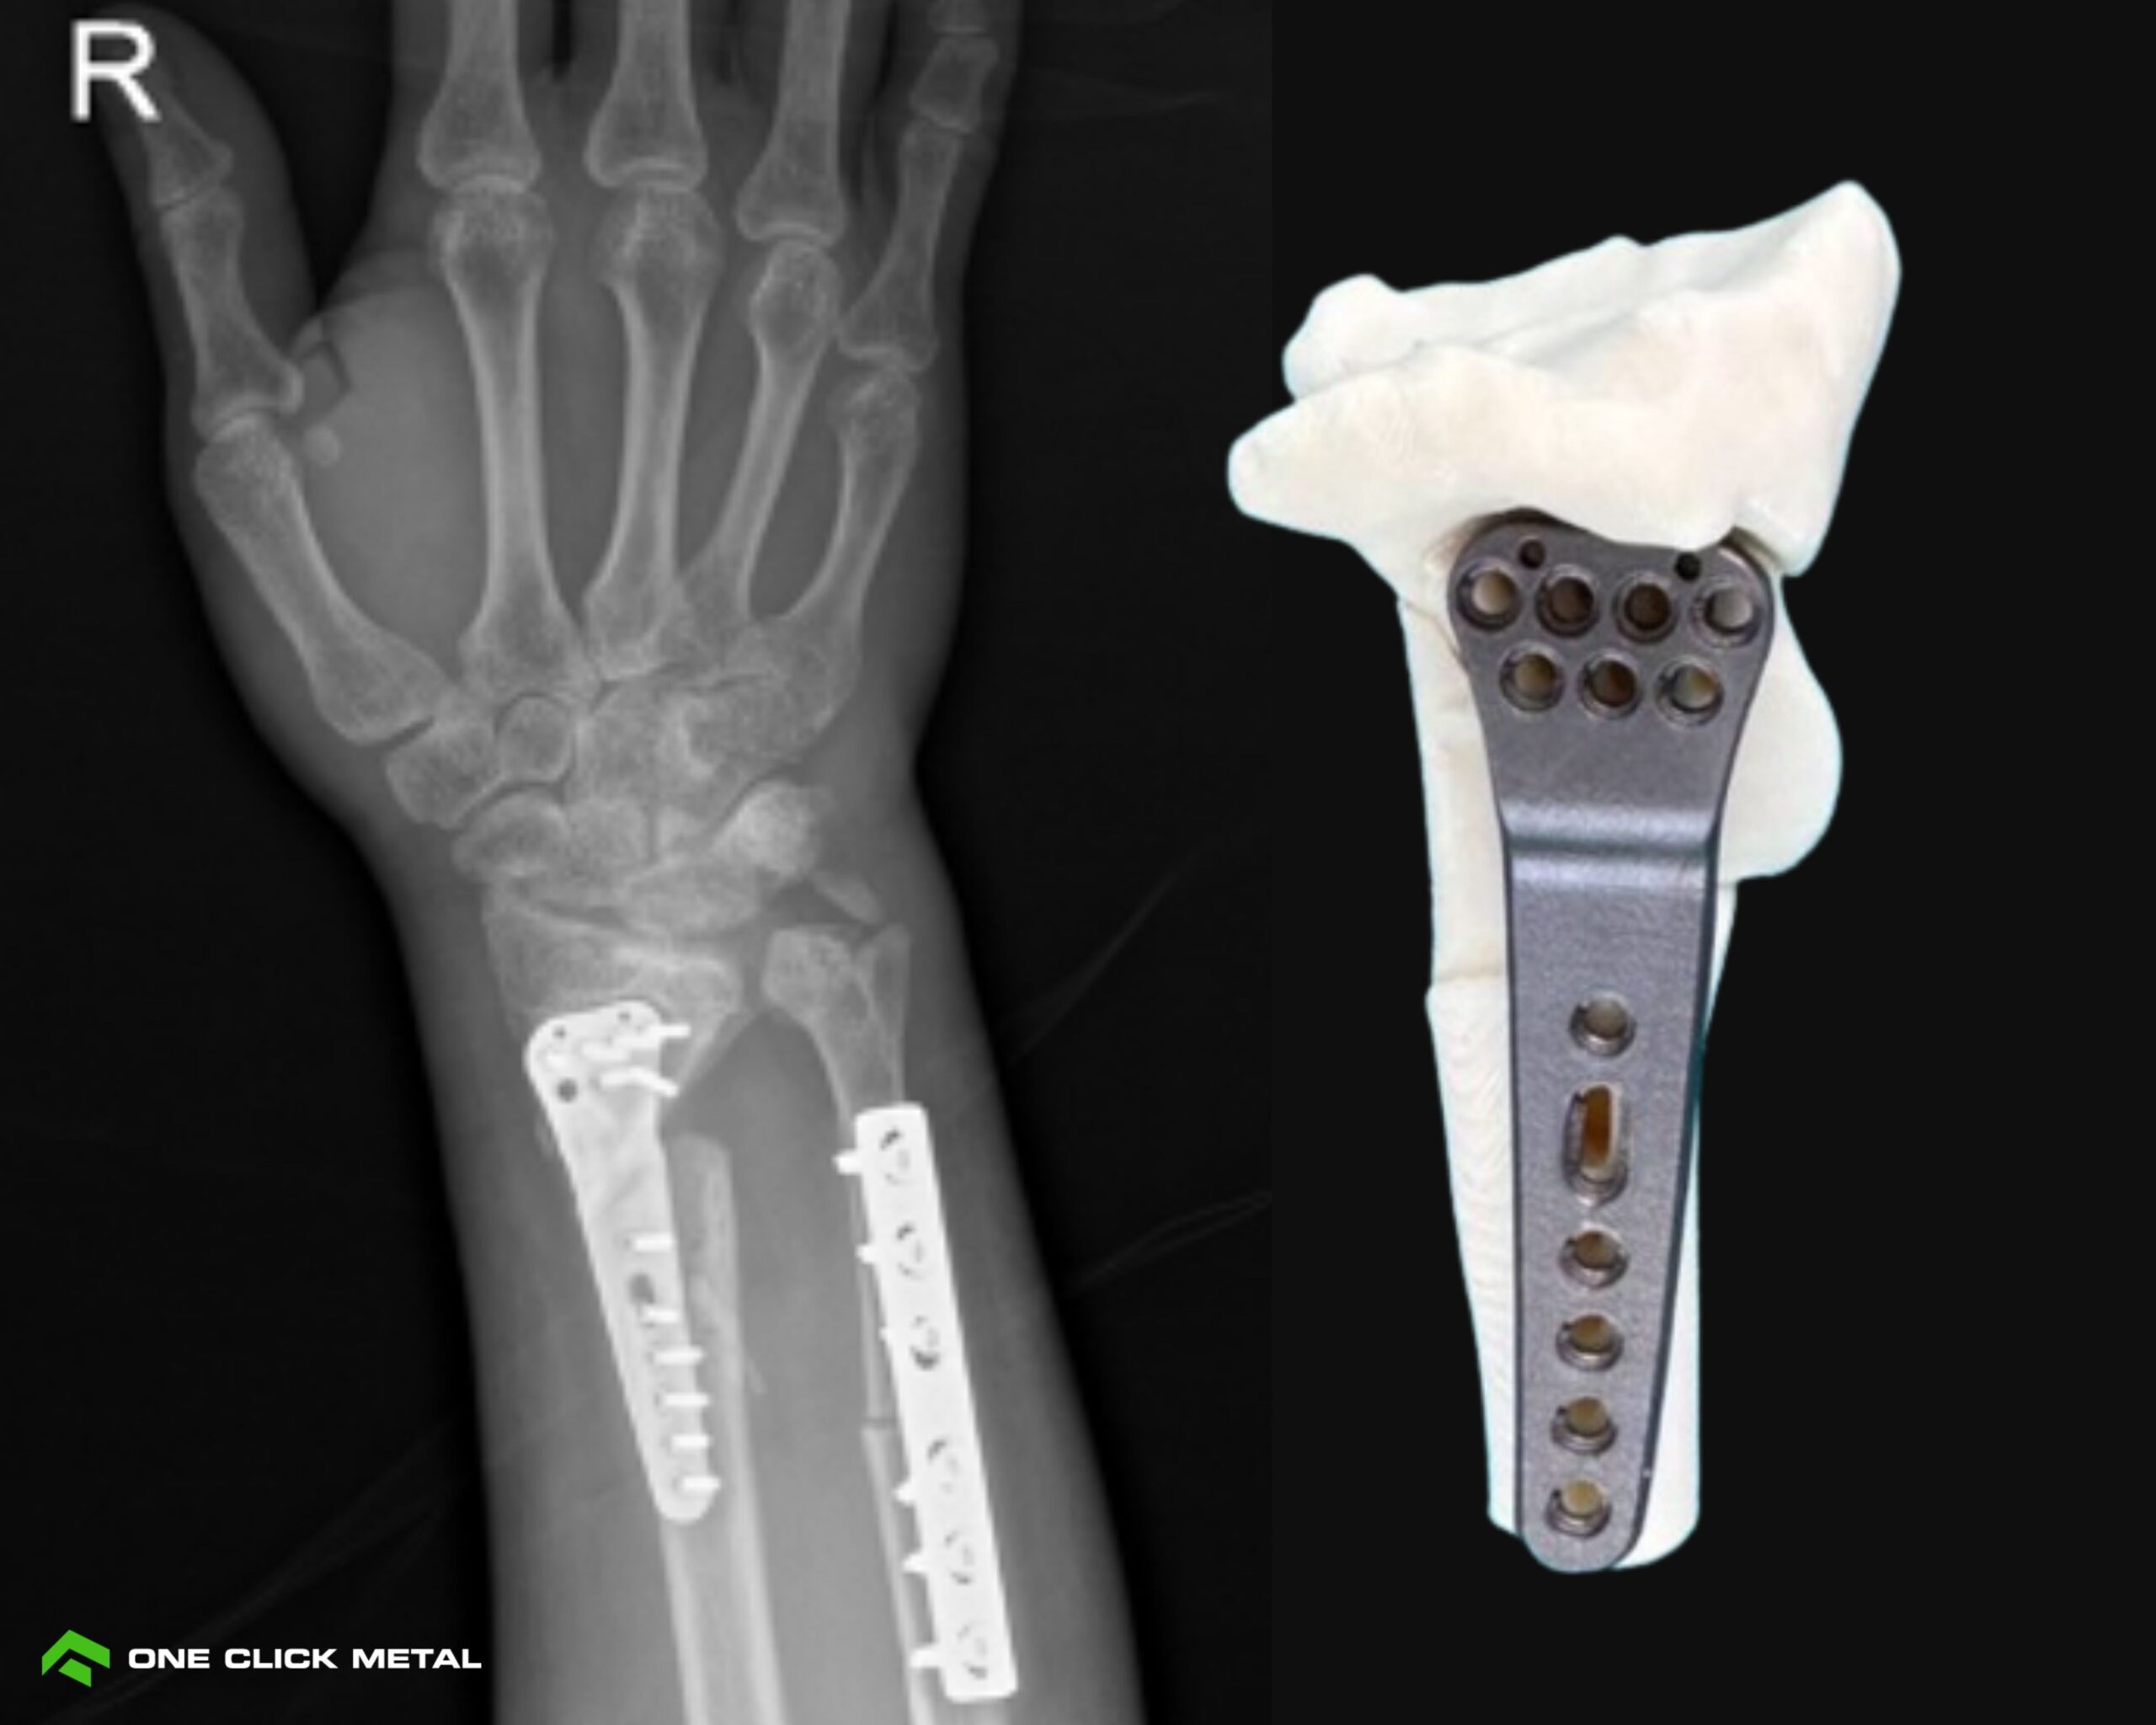

Patient-Specific Distal Radius Plate: Customized for Bone Geometry

Customer: Lerdsin Hospital, Bangkok (Thailand)

Material: Ti6Al4V

Print Time: 1h 37min per part

This custom distal radius plate is tailored exactly to the patient’s wrist anatomy, an ideal case for patient-specific implants. The precise geometry improves fixation, reduces operating time, and lowers overall treatment cost.